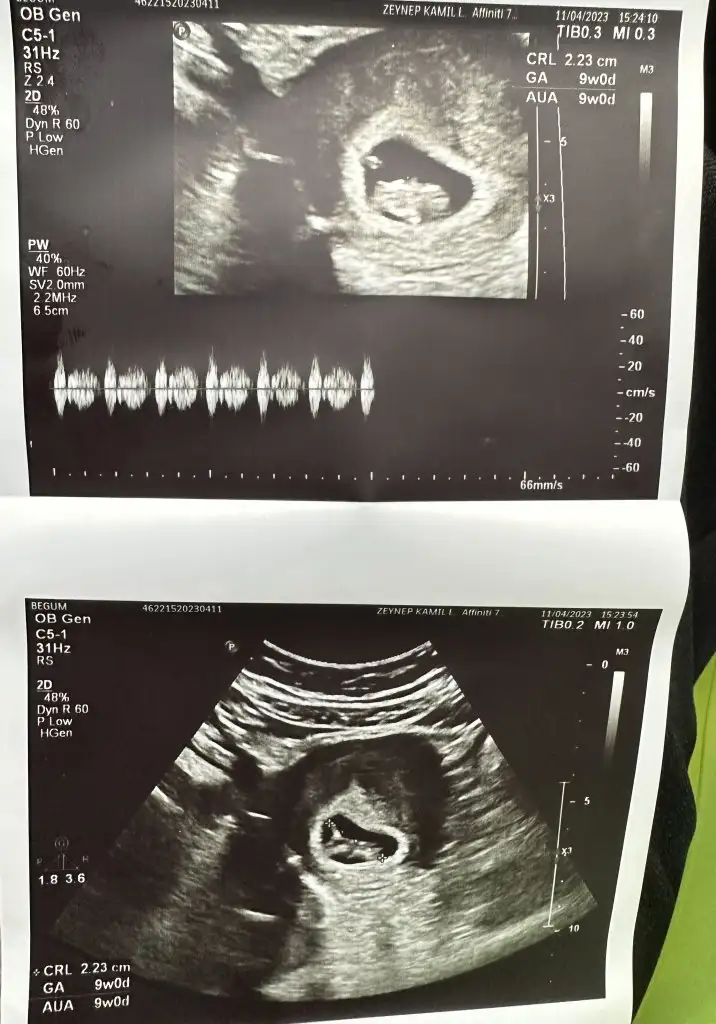

Valla cihaz beni şoke etti son model çıktı ilk defa karından bakıldı özeldeki doktorum 12.haftaya kadar vajinal bakmayı tercih ediyormuş karından bu kadar net olması şaşırttı

Zeynep kamil iyidir ya burası berbat hatta ben usg fotosu bıle vermedıklerını dusundum çünkü gecen gittiğimde aaa kese cok kucuk aaa bebek göremiyorum dedi baktı hıc bısı vermedı yolladı Ama şöylede bişey var teee o haftada gobekten ufacıkta olsa keseyı net gördü bak şiödi hatırladım . Neyse yarına az kaldı